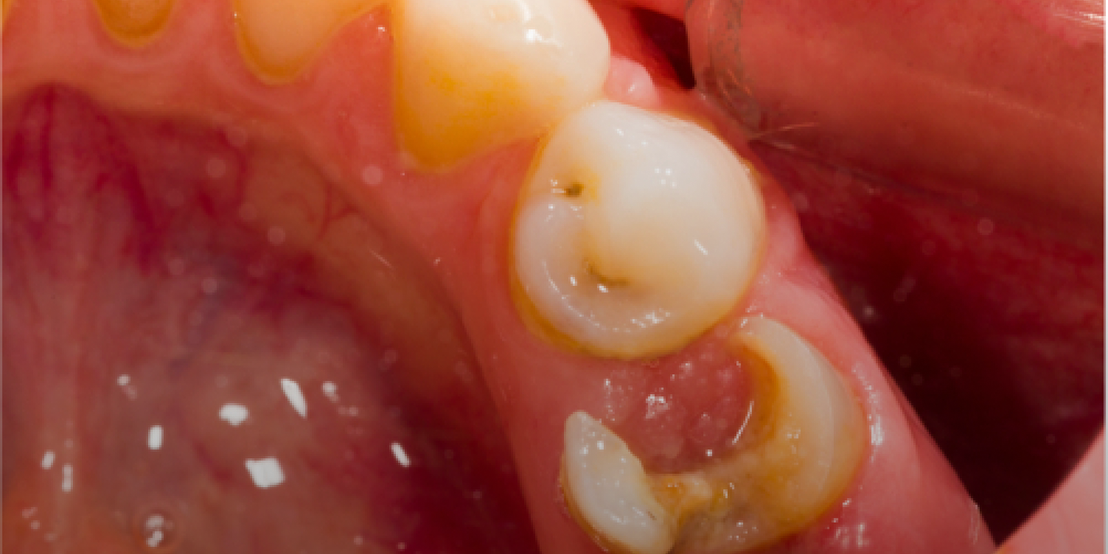

Root canal therapy removes infected pulp while preserving the natural tooth, offering pain relief and preventing further issues. At our clinic, we perform root canal Dubai procedures using advanced tools for accurate cleaning and long-term results.

In cases of severe pain, we offer emergency root canal Dubai services to treat infections promptly. Our team follows proven root canal treatment steps in Dubai to ensure your comfort and a smooth recovery. A crown is placed afterward to restore function and protect your natural smile.

Our modern root canal Dubai is designed to relieve discomfort while preserving your natural tooth. Using advanced technology and a gentle root canal treatment steps Dubai, we effectively remove infection and seal the area to ensure long-term strength and protection. This treatment restores function and comfort with minimal downtime, helping you maintain a healthy, confident smile. +97145641222